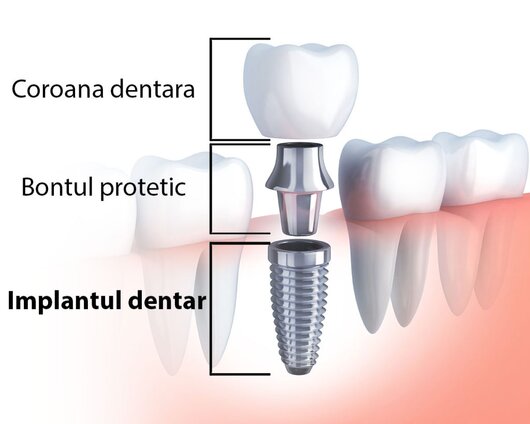

Parodontoza (sau paradontoza) ... | | | | | |  Implant dentar Implant dentar |  | Dentistry Kraft - Clinica stomatologica Non Stop, Bucuresti

Un implant dentar es ... | | | | | |  Fatete dentare Fatete dentare |  | Dentistry Kraft - Clinica stomatologica Non Stop, Bucuresti